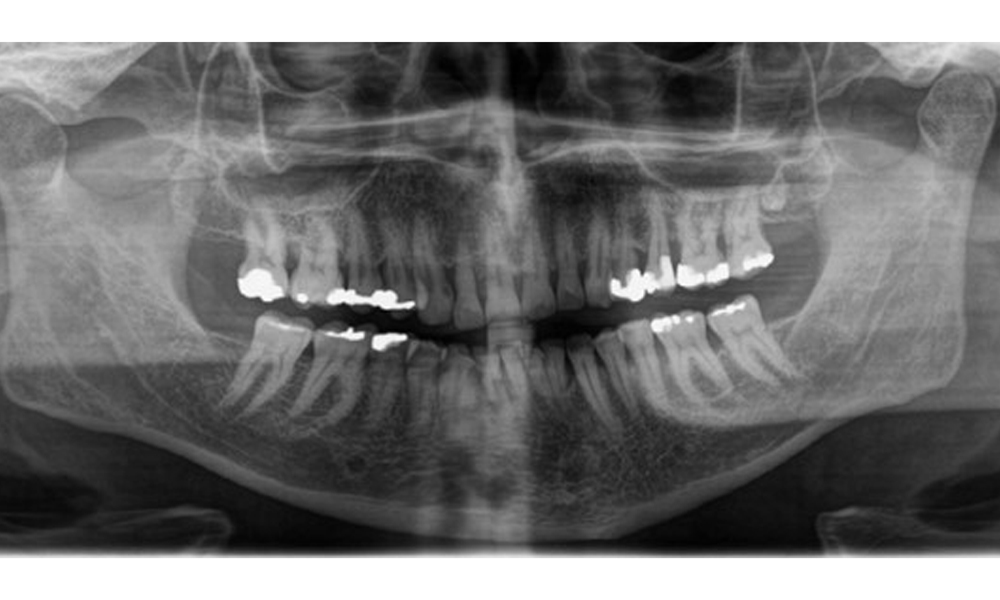

Пациентът има пълно съзъбие с 28 зъба, което включва амалгамни и композитни пломби в областта на моларите и премоларите. На зъб 14 има видима клинична маргинална празнина. Зъб 27 има адекватна златна инкрустация. Налице са и генерализирани атриции и абразии. (фиг. 2, фиг. 3, фиг. 4, фиг. 5, фиг. 6)

Пациентът е с пародонтит II стадий, степен В (5). Клиничните дълбочини на сондиране от 1 до 3 mm са във физиологичния диапазон. Локализирани дълбочини на сондиране от 5 mm са наблюдавани медиопалатинално на 17 и 27. Налице са генерализирани рецесии от 1 до 3 mm с частична загуба на интердентални папили (фиг. 2, фиг. 3, фиг. 4)

Рентгенологични резултати

Налице е пълно съзъбие на възрастен човек с генерализирана костна загуба между 20-50% и множество зони на вертикална костна загуба. Рентгенологичното изследване не разкрива видими кариозни лезии. (Фиг. 7)